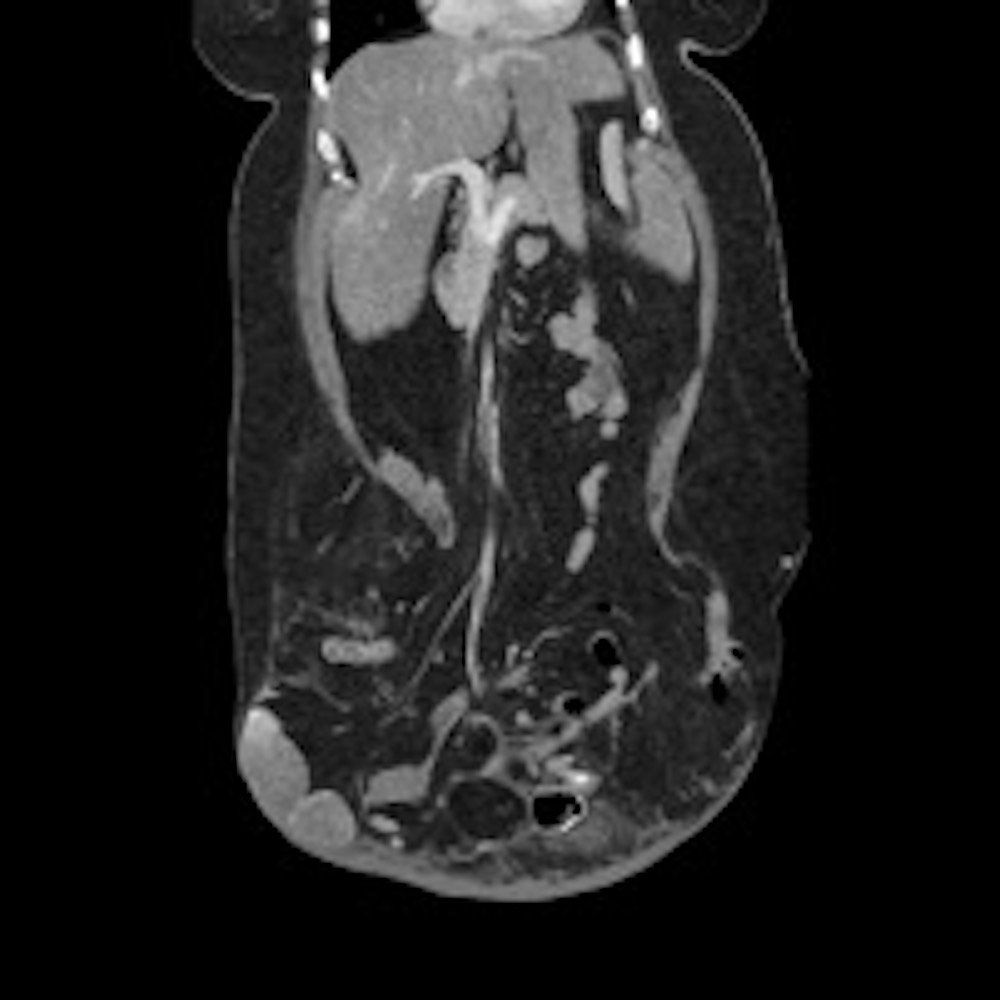

Computed tomography (CT) scan with intravenous (IV) contrast of the abdomen and pelvis demonstrated a large pannus containing a ventral hernia with abdominal contents extending below the knees (white circle), elongation of mesenteric vessels to accommodate abdominal contents outside of the abdomen (white arrow) and air fluid levels (white arrow) indicating a small bowel obstruction.